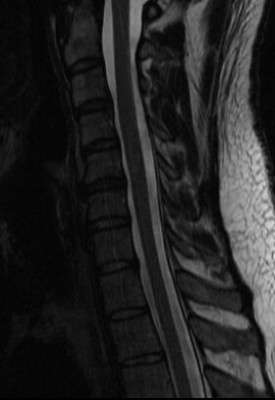

Nyakamon kicsik de sok van,

Hátamba kettő, ebből az alsó eléri a gerincvelőt,

Derekam szanaszét trancsírozva, foramen szűkületek, deformált, stb,

Legutóbbi rtg. idegsebész elismerte hogy a felvételen is látszik az erősen jobbra dőlő gerinc kénszertartása, ami a fájdalmat jelzi és hogy baj van. De hogy mi a baj azt nem tudja.Hogy ezekből ki mit látott meg ki mit nem, azt nem tudom. De ha műteni akarnak nem fogok bele egyezni. Elég volt a segítségükből.

elég érdekes, mri-t jó lenne látni, mégis mi az, ami nem utal műtétre, de gondot okoz.

mi nyomja akkor az ideget? a csavarok? -